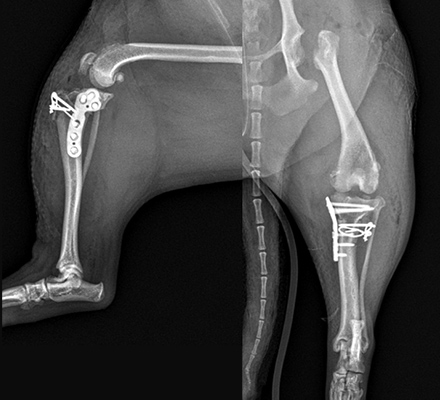

제주도에서 수술 받으러 온 율무 십자인대 TPLO 후기

바닷가 산책 중 율무가 땅에 다리를 딛지 못해 집근처 병원을 방문했더니 ‘십자인대 단열’을 진단 받았고 수술이

필요하다는 소견을 들었습니다. 해당 병원에서는 7년 전 슬개골 수술로 pin이 박혀있어 TPLO는 불가능하고

다른 방법도 까다롭고 어렵다는 얘기를 들었습니다.

그래서 정형외과 수술로 유명한 예은동물의료센터, 특히 권기범 원장님께 카톡으로 x-ray를 보내 상담을 신청했고

TPLO가 가능하며 빠르게 수술일정을 잡아주셨습니다. 제주에 사는 저희는 당장 서울로 갔습니다.

수술당일 권기범 원장님께서 수술방법을 아주 자세하고 친절하게 설명해주셨습니다.

마취과 전문의가 상주하는 것도 안심이 됐고 수술전 검사도 꼼꼼했습니다.

수술 중 율무는 절개도 최소화했고 출혈도 거의 없었으며 혈압과 맥박도 안정적이었다고 들었습니다.

실시간 수술상황을 모니터로 볼 수 있었던 것도 큰 신뢰감을 주었어요. 또한 수술과정을 설명과 함께 사진을 제공

해주셨고 모든 과정이 체계적이었고 그 덕에 율무는 다음날 바로 네발로 배변할 정도로 회복이 빨랐습니다.

재활방법도 유튜브에 있어 제주에 있는 저희도 손쉽게 따라 할 수 있고 카톡상담도 편리했습니다.

덕분에 율무는 다시 제주 바다를 힘차게 걷고 있어요. 감사합니다.